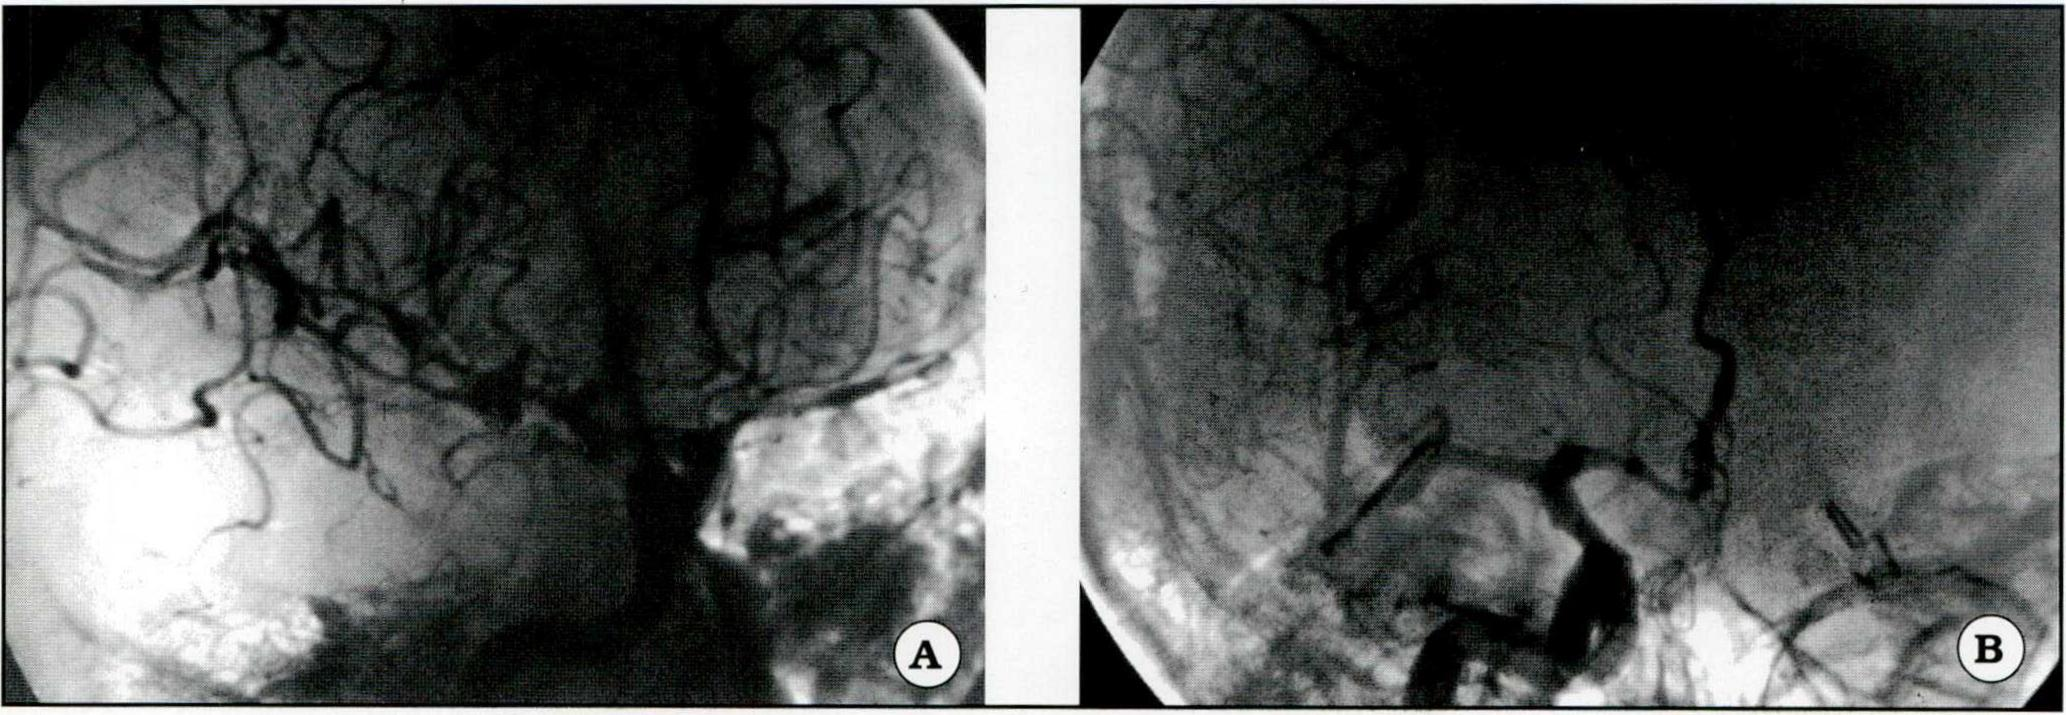

Fig 4. A. Angiograma preoperatorio de un aneurisma del apex de la arteria basilar (proyección perfil). B. Angiorresonancia de control postoperatorio correspondiente al aneurisma basilar, con exclusión del mismo por clipado.